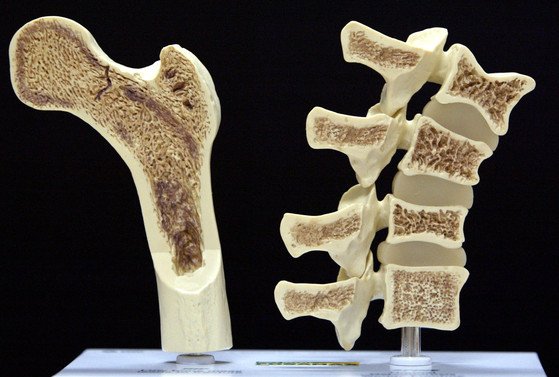

골다공증에 좋은 음식 10가지에 대하여서 살펴보겠습니다. 골다공증은 뼈의 밀도가 감소되어서 쉽게 골절이 일어나는 질병이고요. 골다공증이 있다면 관절 통증 및 보행에 곤경을 느낄 수 있다고 합니다. 이러한 골다공증에 좋은 음식 10가지를 확인해 보시기 바랍니다!